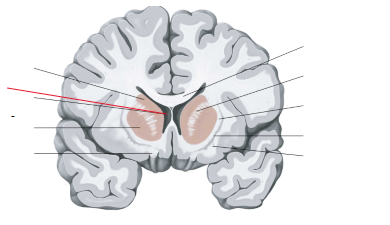

nucleus caudatus

putamen

globus pallidus

capsula interna (corona radiata)

laterale ventrikels (I en II)

septum pellucidum